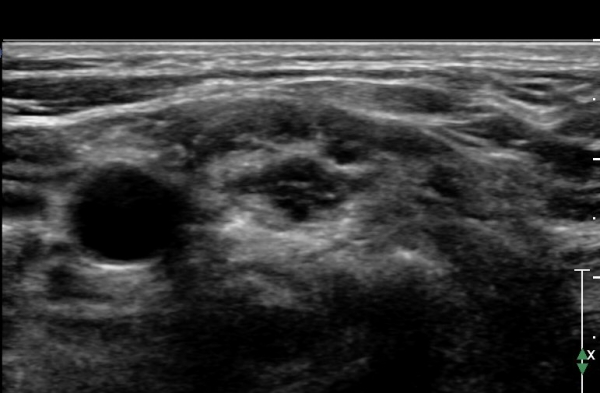

ÃÊÀ½ÆÄ °Ë»ç :  ÁÂÃø ¸ñ ¾Õ ¿ÜÃø¿¡¼­ °üÂûÇÑ Á¦5°æÃß ½Å°æ±Ù Ⱦ´Ü¸é°Ë»ç¿¡¼­ Á¦5°æÃß ½Å°æ±ÙÀÇ °æ¹ÌÇÑ Àú¿¡ÄÚ

ºÎÁ¾ÀÌ °üÂûµÊ(»çÁø 1).